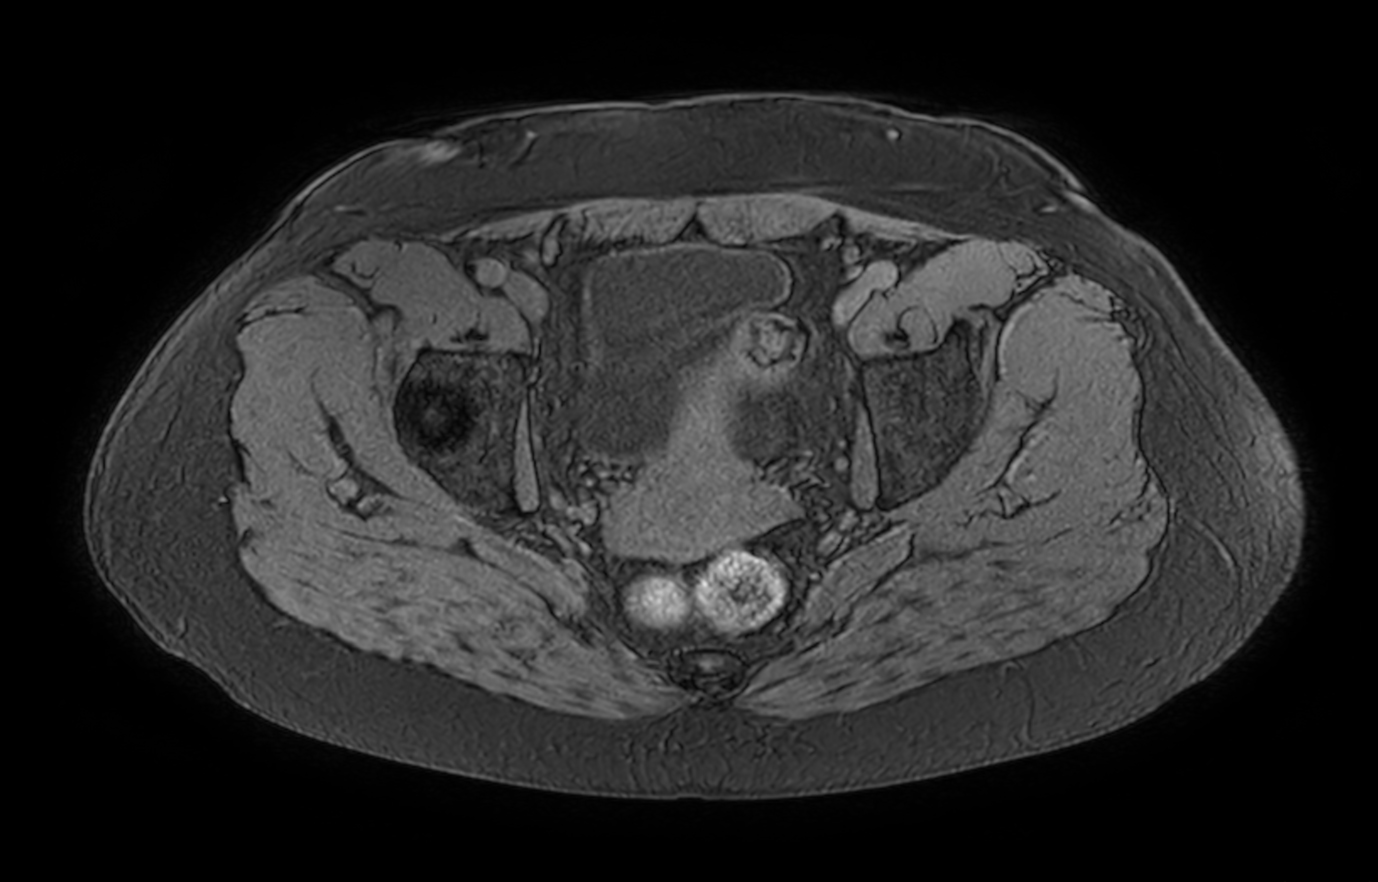

Axial T1w FFE mDIXON XD (Water only)